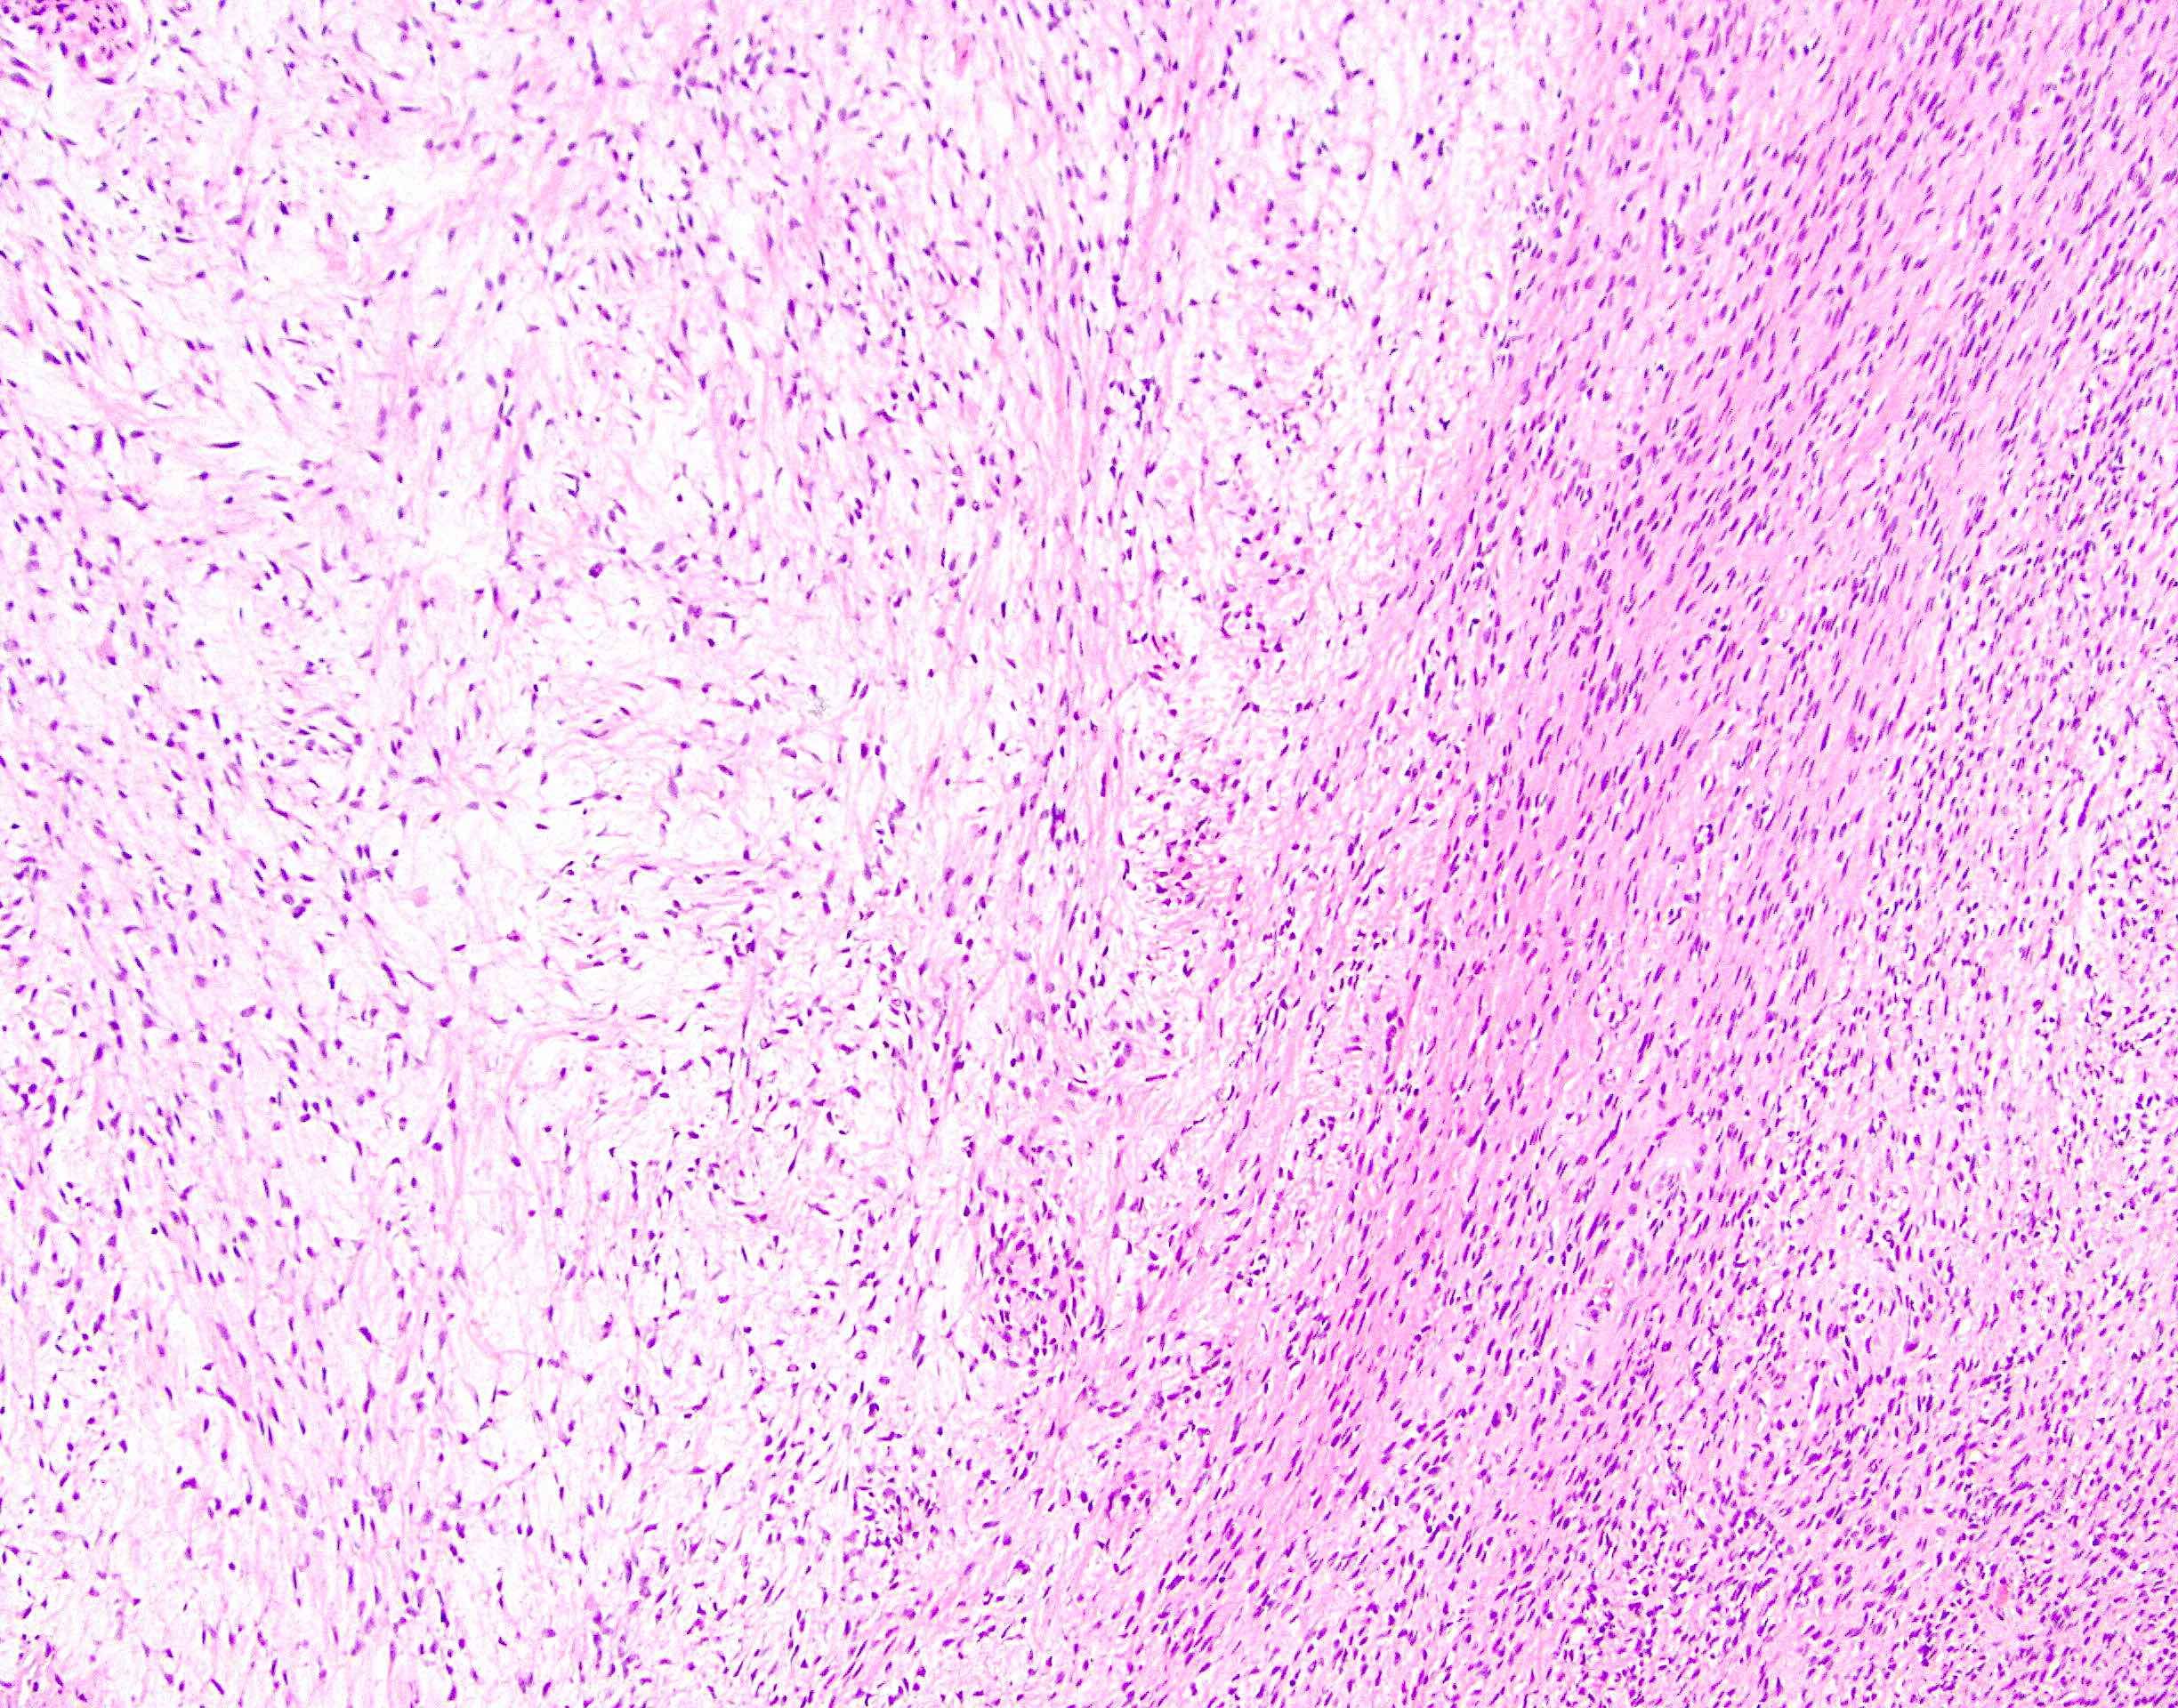

Microscopic (histologic) description

- Low to moderately cellular, bland fusiform or spindled cells with focal to diffuse whirling in heavily collagenized stroma with abrupt transition to myxoid areas

- 45% have epithelioid areas

- 40% contain poorly formed but large collagen rosettes

- Often infiltrates adjacent skeletal muscle

- Occasionally has areas of increased cellularity, atypia, necrosis or mitotic activity characteristic of intermediate to high grade sarcoma

- Recurrences may show increased cellularity and mitotic activity

Microscopic (histologic) images